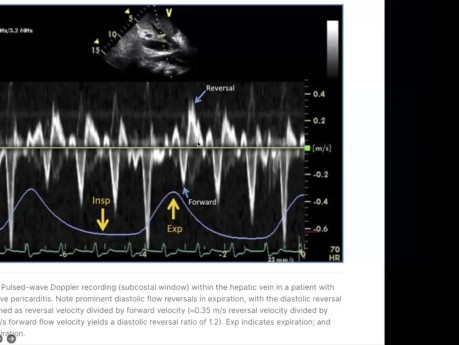

Ocena echokardiograficzna i diagnostyka zaciskającego...

Ocena echokardiograficzna i diagnostyka zaciskającego zapalenia osierdzia. Prelegent: Dr Muizz Wahid, Cardiology Resident, University of Toronto. Cele: 1. Informacje ogólne na temat zaciskającego zapalenia...